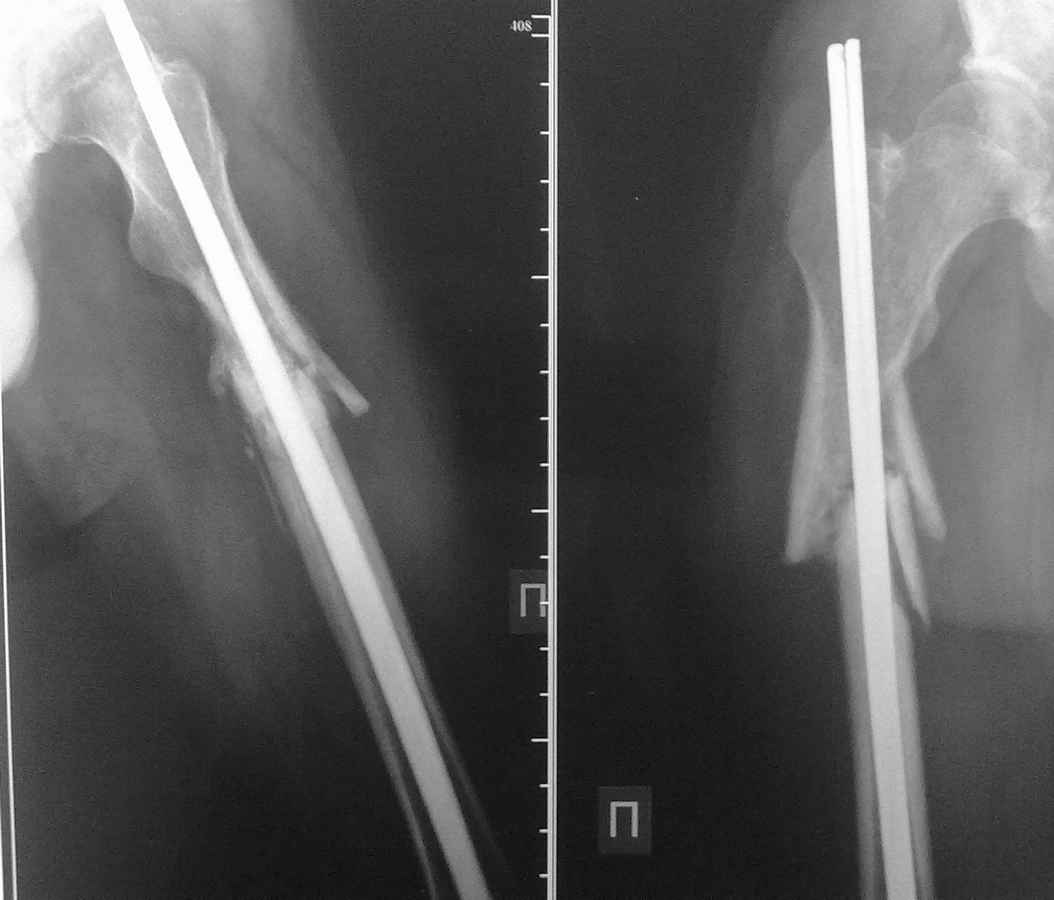

у пациента 24 лет после перелома бедра в ноябре 10г. и остеосинтеза двумя титановыми

стержнями наступило вторичное смещение отломков и миграция стержней, укорочение 5 см

посылаю Рг-граммы и прошу Вашего мнения по тактике дальнейшего лечения, имеются

расхождения во мнениях...